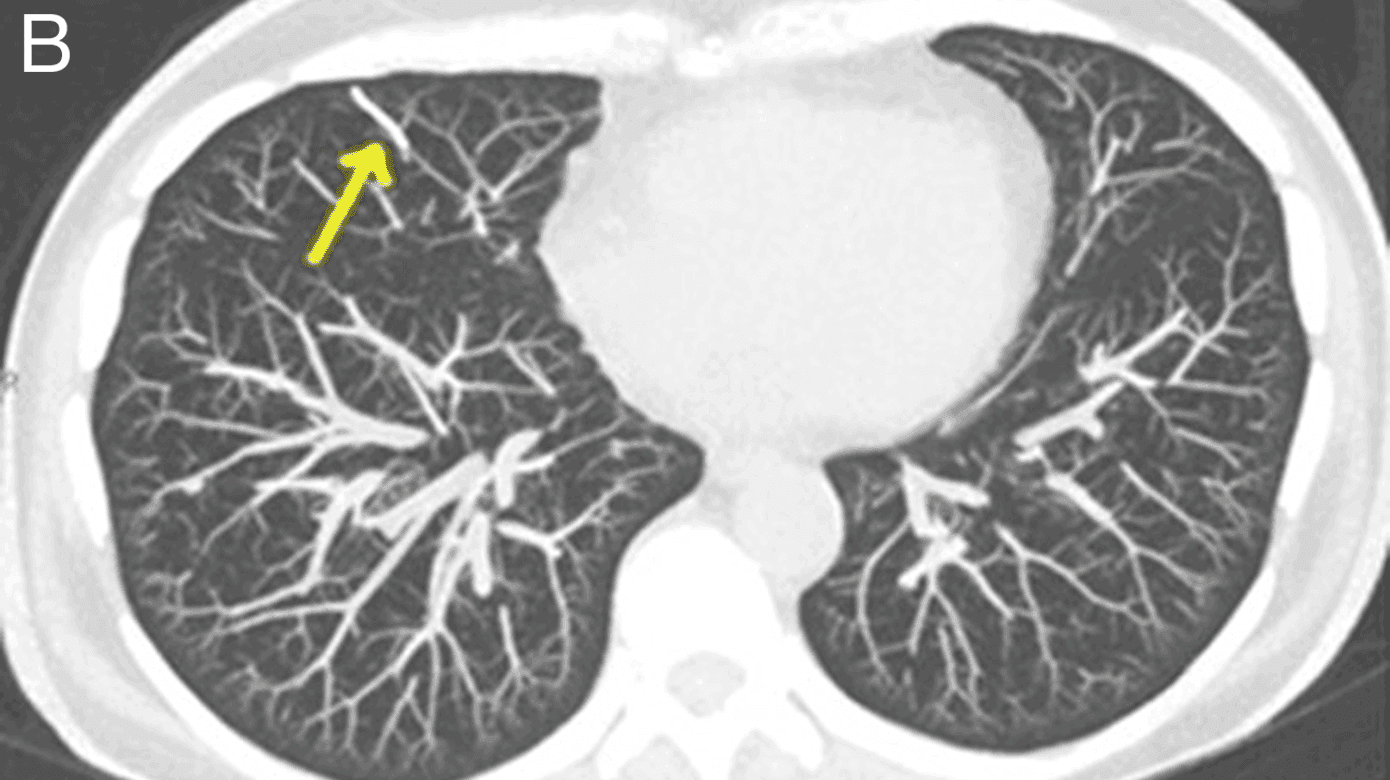

En 57-årig kvinde med cancer mammae sinister uden metastasering i forløb med neoadjuverende kemoterapi blev indlagt i akutmodtagelsen, da hun under MR-skanning udviklede varmefornemmelse og smerter i højre side af brystet. Skanningen blev afbrudt akut, og symptomerne forsvandt. Objektiv undersøgelse og blodprøver gav ingen afklaring. Røntgenundersøgelse af thorax viste et 18 mm langt fremmedlegeme i højre mellemlap (A). CT bekræftede et hyperdenst fremmedlegeme (B), mest sandsynligt i en subsegmental gren af a. pulmonalis til højre lunges mellemlap.